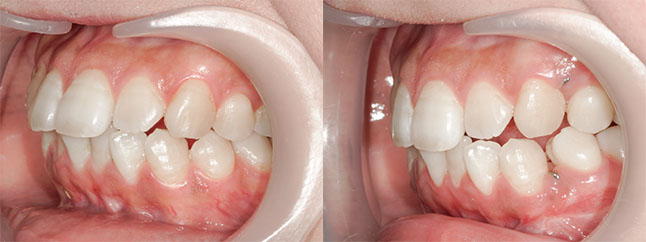

【治療内容】出っ歯、口元の膨らみが気になると当院を受診されました。上の前歯と歯茎が前方にポジショニングしており、下の前歯も歯茎から前に出ておりました。

<上下セットバック>

歯と歯茎を上は、5oバック、2oアップ、下は5oバックし固定しました。

※口ゴボ感が改善し、ご満足いただけました。

※afterは術後3か月時の写真です。

【費用】上下セットバック 2,307,800円(税込)

【リスク】感染・腫れ・出血・知覚鈍麻など